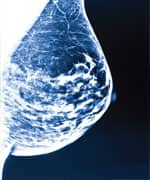

To fully understand the carcinogenic effects of aging, we have reprinted the chart below showing women’s breast cancer risk by age.29A quick look at this chart clearly documents that aging is a primary cause of breast cancer, not hormones like estrogen. If estrogen caused breast cancer, then we would expect to see very high rates of breast cancer in young women of childbearing age, with a dramatic decrease in breast cancer after menopause. This is not observed. The good news is that many of the gene expression changes involved in the development of breast and other cancers can be favorably altered by taking low-cost nutrients like vitamin D40,105,106 in the dose of 1,000 to 10,000 IU/day, based on individual response.